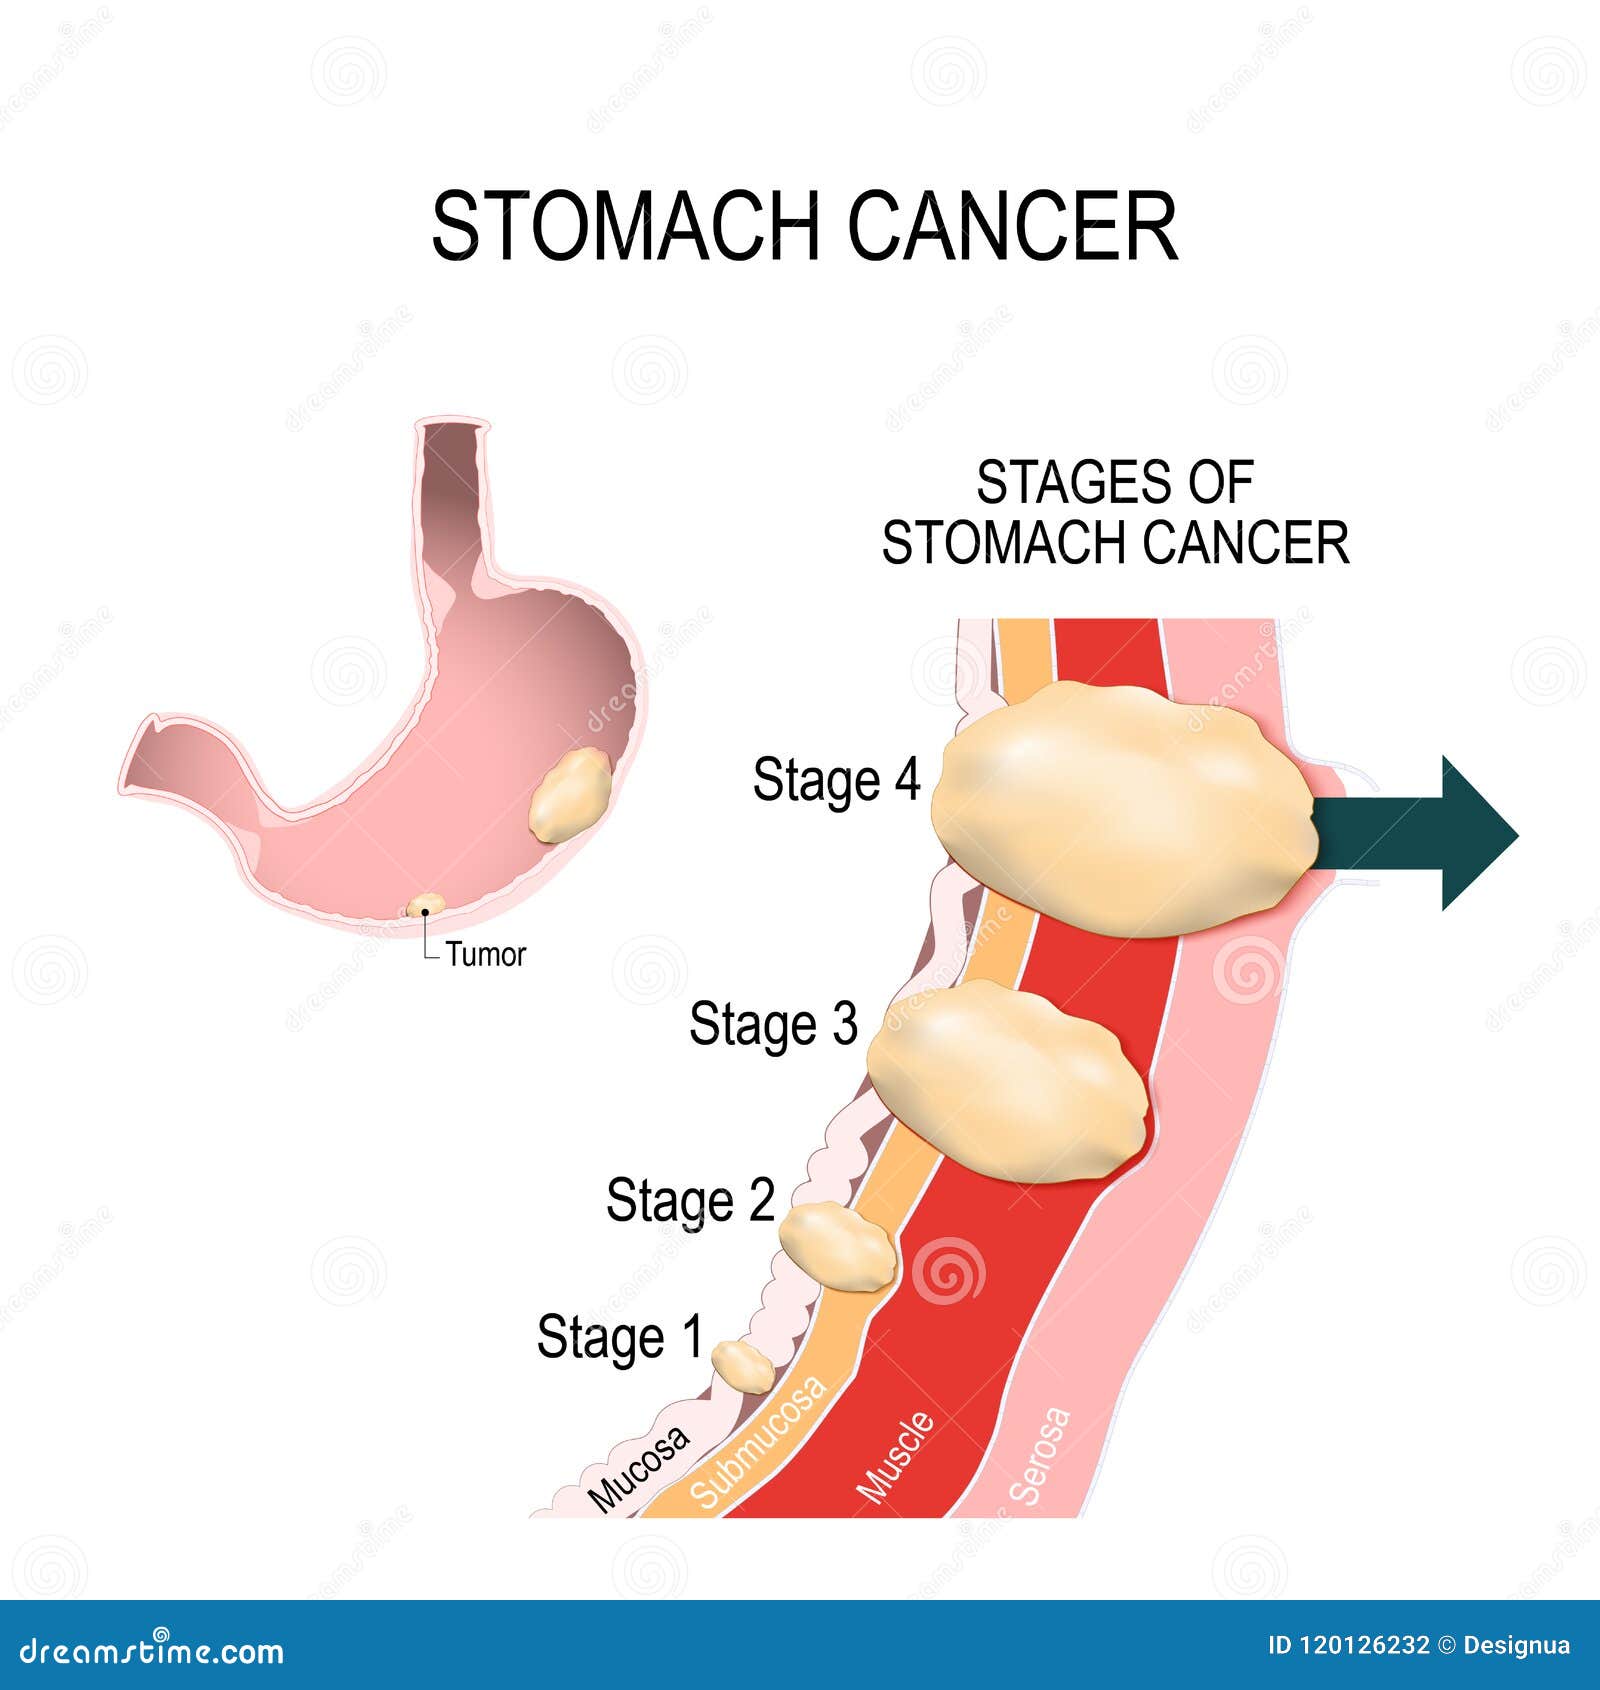

Stages of stomach cancer Royalty Free Vector Image

Stomach Cancer. Vector Illustration for Medical Use Stock Vector …

Vector Isolated Illustration of Stomach Cancer Stock Vector …

Vector Isolated Illustration of Stomach Cancer Stock Vector …